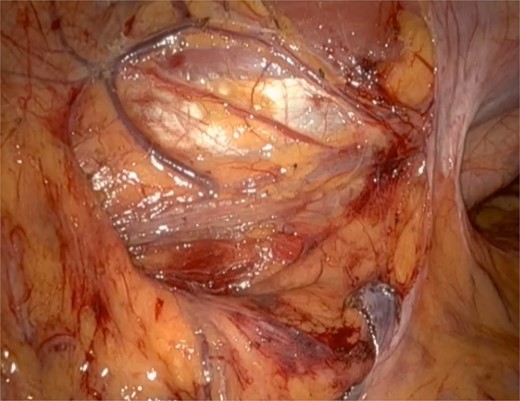

He underwent a robotic excision of his paraganglioma in a right lateral position, using a transperitoneal approach with three robotic ports and one assistant port in the midline. The left colon was mobilized medially, exposing the tumour. After identifying the ureter and gonads, the tumour was dissected freely using a vessel sealer, before removing it in a specimen bag. Operation was uneventful (Figs 3 and 4).

Well circumscribed mass with extensive vascularisation is located and isolated, with no surrounding tissue necrosis or invasion observed. Real time video footage revealed a pulsatile mass.

Post tumour removal showed clean base with no active bleeding. No evidence of tissue invasion into peripheral structures.